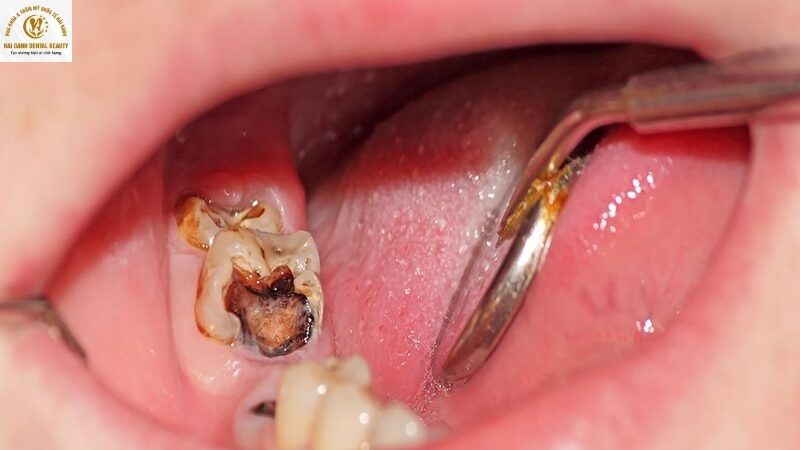

- Hướng mọc: Ngược lại, nếu răng khôn bị sâu nghiêm trọng, đã ăn vào tủy răng, hoặc mọc ở những vị trí phức tạp như mọc lệch, mọc ngầm, thì việc nhổ bỏ là giải pháp tối ưu. Việc cố gắng trám một chiếc răng khôn mọc lệch không chỉ tốn kém mà còn không giải quyết được nguyên nhân gốc rễ, khiến sâu răng dễ tái phát, lây lan sang răng bên cạnh.

2.2. Nguy cơ biến chứng và tầm ảnh hưởng đến các răng khác

Răng khôn bị sâu không chỉ là vấn đề của riêng nó mà còn là mối đe dọa với sức khỏe răng miệng tổng thể. Khi răng khôn bị sâu nặng, vi khuẩn có thể lan truyền, gây sâu răng số 7 bên cạnh hoặc viêm nhiễm mô mềm. Thậm chí, một chiếc răng khôn mọc ngầm và bị sâu có thể hình thành u nang, tiêu xương hàm, ảnh hưởng đến dây thần kinh và gây đau đớn dữ dội.

Với những trường hợp này, việc nhổ bỏ răng khôn là cách duy nhất để điều trị triệt để, ngăn chặn những biến chứng nguy hiểm và bảo vệ toàn bộ cung hàm.